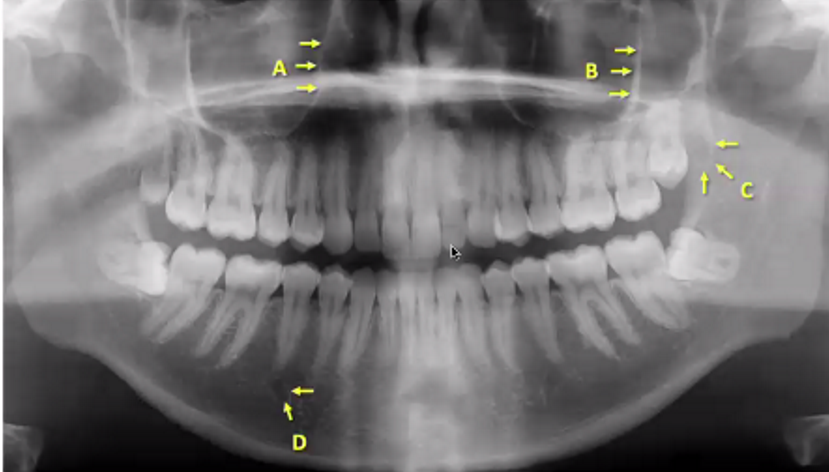

A

medial wall of maxillary sinus (right)

B

zygomatic process/buttress

C

maxillary tuberosity

D

mental foramen